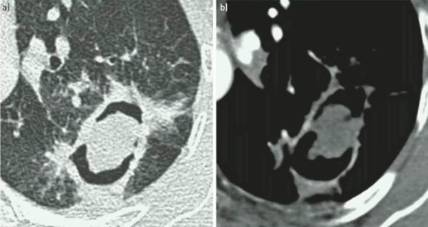

单纯肺曲菌球:非免疫受损病人,有较少或没有症状,含真菌球单发空洞,具有曲霉菌血清学和微生物学依据(阳性结果),至少视察3个月没有放射影像学的进展。

慢性空洞性肺曲霉病(CCPA):最常见,单发或多发的肺空洞(薄壁或厚壁),空洞内可包含一个或多个曲菌球或不规则的腔内物质,具有曲霉菌血清学和微生物学依据,并有明显肺部和全身症状,至少3个多月的视察有放射影像学进展(新发空洞,空洞外周浸润增加及纤维增生增加)。

亚急性侵袭性肺曲霉病(SAIA):轻度免疫缺陷的侵袭性肺曲霉病患者,发生在1-3个月内,具有可变的影像学特征,包括空洞、结节、有“脓肿形成的进展性实变”。最重要的特征为肺组织发现菌丝,另血液或呼吸液GM试验呈强阳性。